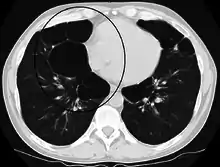

A severe case of bullous emphysema

Axial CT image of the lung of a person with end-stage bullous emphysema